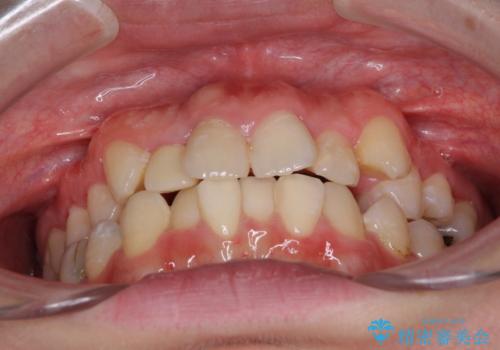

- 上下のデコボコと奥歯の咬みにくさを気にして来院された患者様です。

上顎骨の幅が下顎骨よりも小さいので、拡大装置により骨幅を広げて上下関係を改善し、その後インビザラインにて歯並びを整えることとしました。